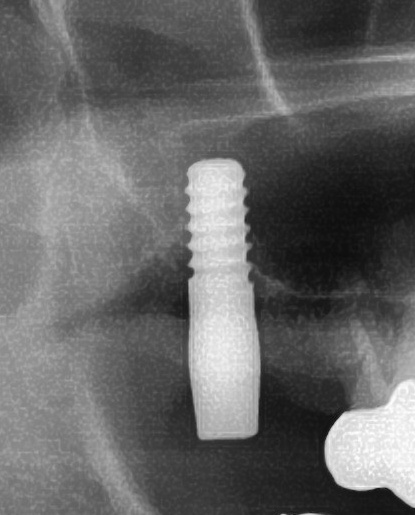

患者様はインプラント植立を希望され、今回、右上7番目の植立が決まりました。

また、骨が薄い部分の上顎の奥歯にインプラントを埋入するための、ソケットリフトという技術を使って骨の厚みを確保し、インプラントを植立することになりました。

骨補填材の上にインプラントを埋入します。

しっかりとインプラント埋め込まれた後は、動揺がないか、噛んだ時に当たらないかなどを確認して、最後にパノラマ写真を撮影して今回のオペは終了となりました。